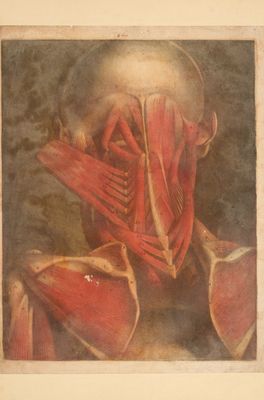

Myologie complette en couleur et grandeur naturelle, composée de l'Essai et de la Suite de l'Essai d'anatomie, en tableux imprimés [d'après les parties disséquées et préparées / par M. Duverney.

- Jacques Fabien Gautier d'Agoty

- 1746[-1748]

Credit: Myologie complette en couleur et grandeur naturelle, composée de l'Essai et de la Suite de l'Essai d'anatomie, en tableux imprimés [d'après les parties disséquées et préparées / par M. Duverney. Source: Wellcome Collection.